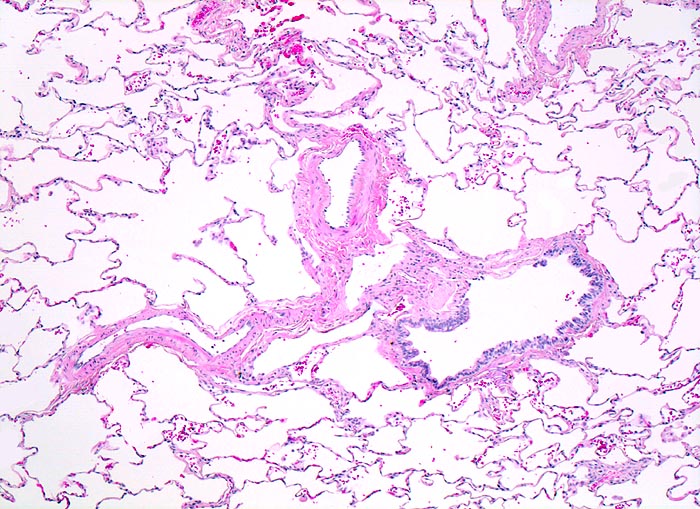

normales Lungenparenchym

Normalbefund

Lunge

Die Alveolarsepten sind sehr schlank. Die

Lungenarterienäste verlaufen zusammen mit den Luftwegen. Im Bild ein

Bronchiolus.

Histologie

50

24

männlich